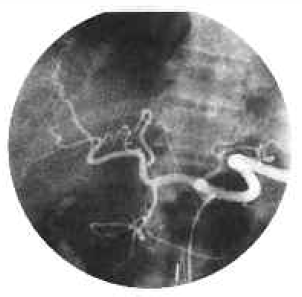

Postoperative immunosuppression consisted of triple drug therapy, namely 2 mg/kg/day azathioprine administered intravenously, with 2.5 mg/kg/day prednisolone and 3 mg/kg/day cyclosporine also administered intravenously. The early postoperative day was uneventful. The child began to recover. Unfortunately, on the third postoperative day, cerebral edema developed, and the liver functions began to show signs of deterioration as well. Therapy with OKT3 2.5 mg/day was started and continued for 5 days. After some improvement of liver functions, progressive deterioration began again, and a hepatic angiogram was performed; this revealed the graft artery and portal vein to be patent (Figure 2a, b). Following severe cerebral edema, the patient became unresponsive to medical treatment. Progressive deterioration of brain and liver functions led to the eventual death of the child on the 14th postoperative day. The postoperative course of the donor was uneventful. A slight elevation of the bilirubin (total, 4.2 mg; direct 3.0 mg) occurred during the first 48 hours, but returned to normal within a couple of days (Table 1), and she was ready to be discharged on the seventh postoperative day. Three months after surgery, she became pregnant and is still doing well.

Figure 2. (a) Postoperative graft arteriogram showing a patent graft artery. Arrow shows inferior mesenteric vein graft. (b) Superior mesenteric arteriogramdemonstrating patent graft portal vein.